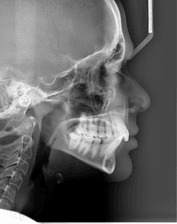

Зъбните снимки, независимо дали са секторни, панорамни зъбни снимки, телерентгенографии или друг вид се съхраняват на нашите сървъри неограничено дълго време.

Денталните медици могат с лекота да правят всички необходими обработки и измервания на дигиталните зъбни снимки, което улеснява подготовката за лечебния процес на пациента.

Дигиталните зъбни снимки са подредени в хронологичен ред. При влизане в досието на пациент се виждат всички негови дигитални зъбни снимки, направени във времето, което дава възможност да се проследи развитието на лечението.